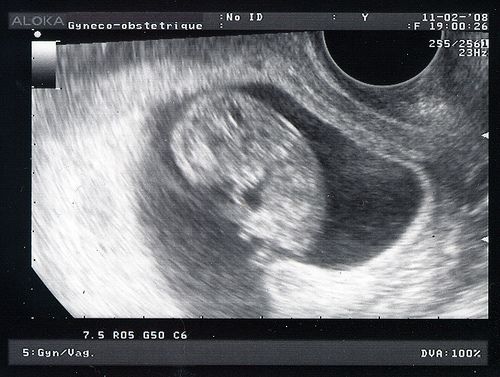

La photo date de lundi dernier, le 11 février, le foetus (puisque maintenant, ce n'est plus un embryon) mesurait 3,6 cm de la tête aux fesses, une nuque toute fine qui nous rassure sur certains problèmes qu'il n'aura pas. Quelques tests à faire pour continuer d'être rassurés, une belle dose de stress et d'inquiétudes, mais surtout une dose massive de bonheur.